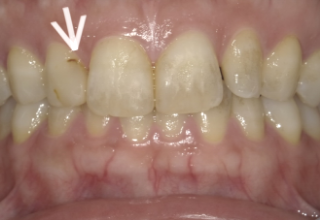

前歯のヒビの症例

症例1

治療方法 ラミネートベニア

治療期間 1ヶ月

治療費用 1歯 110,000×8本 ¥880,000(税込)

処置料金 ¥16,500

総額 ¥896,500(税込)

※治療当時の価格です

治療の副作用.リスク 歯ぎしりや食いしばりが強いと欠けることがある

ラミネートベニア

前歯のヒビと色素沈着がお悩みでした。ホワイトニングの効果がでにくい歯の質の場合は、ヒビを補強して質感を整えられるラミネートベニア法が最適です。上顎8本のラミネートベニア法で治療を行いました。元々食いしばり癖がヒビの原因になっている経緯があったため、治療後のマウスピース装着で歯を守り、ボトックス注入で咬合力コントロールを行っています。